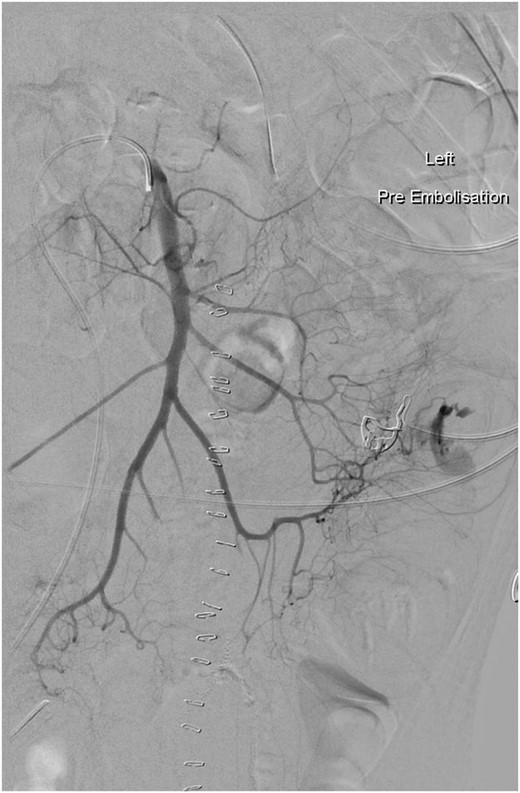

A week post-operatively he developed recurrent rectal bleeding. A colonoscopy, red blood cell (RBC) scan and CT angiography (CTA) were performed but failed to localize the site. Later that day he had further episodes of large volume rectal bleeding and a repeat CTA identified the jejunal anastomosis as the site of bleeding (Fig. 1). He underwent table endoscopy and re-laparotomy and the anastomosis was resected and the jejunum re-anastomosed. Post-operatively the bleeding settled and he was discharged home 2 weeks later.

Arteriogram showing active bleeding from branch of the superior mesenteric artery into the jejunum (arrowed), which was subsequently embolized.